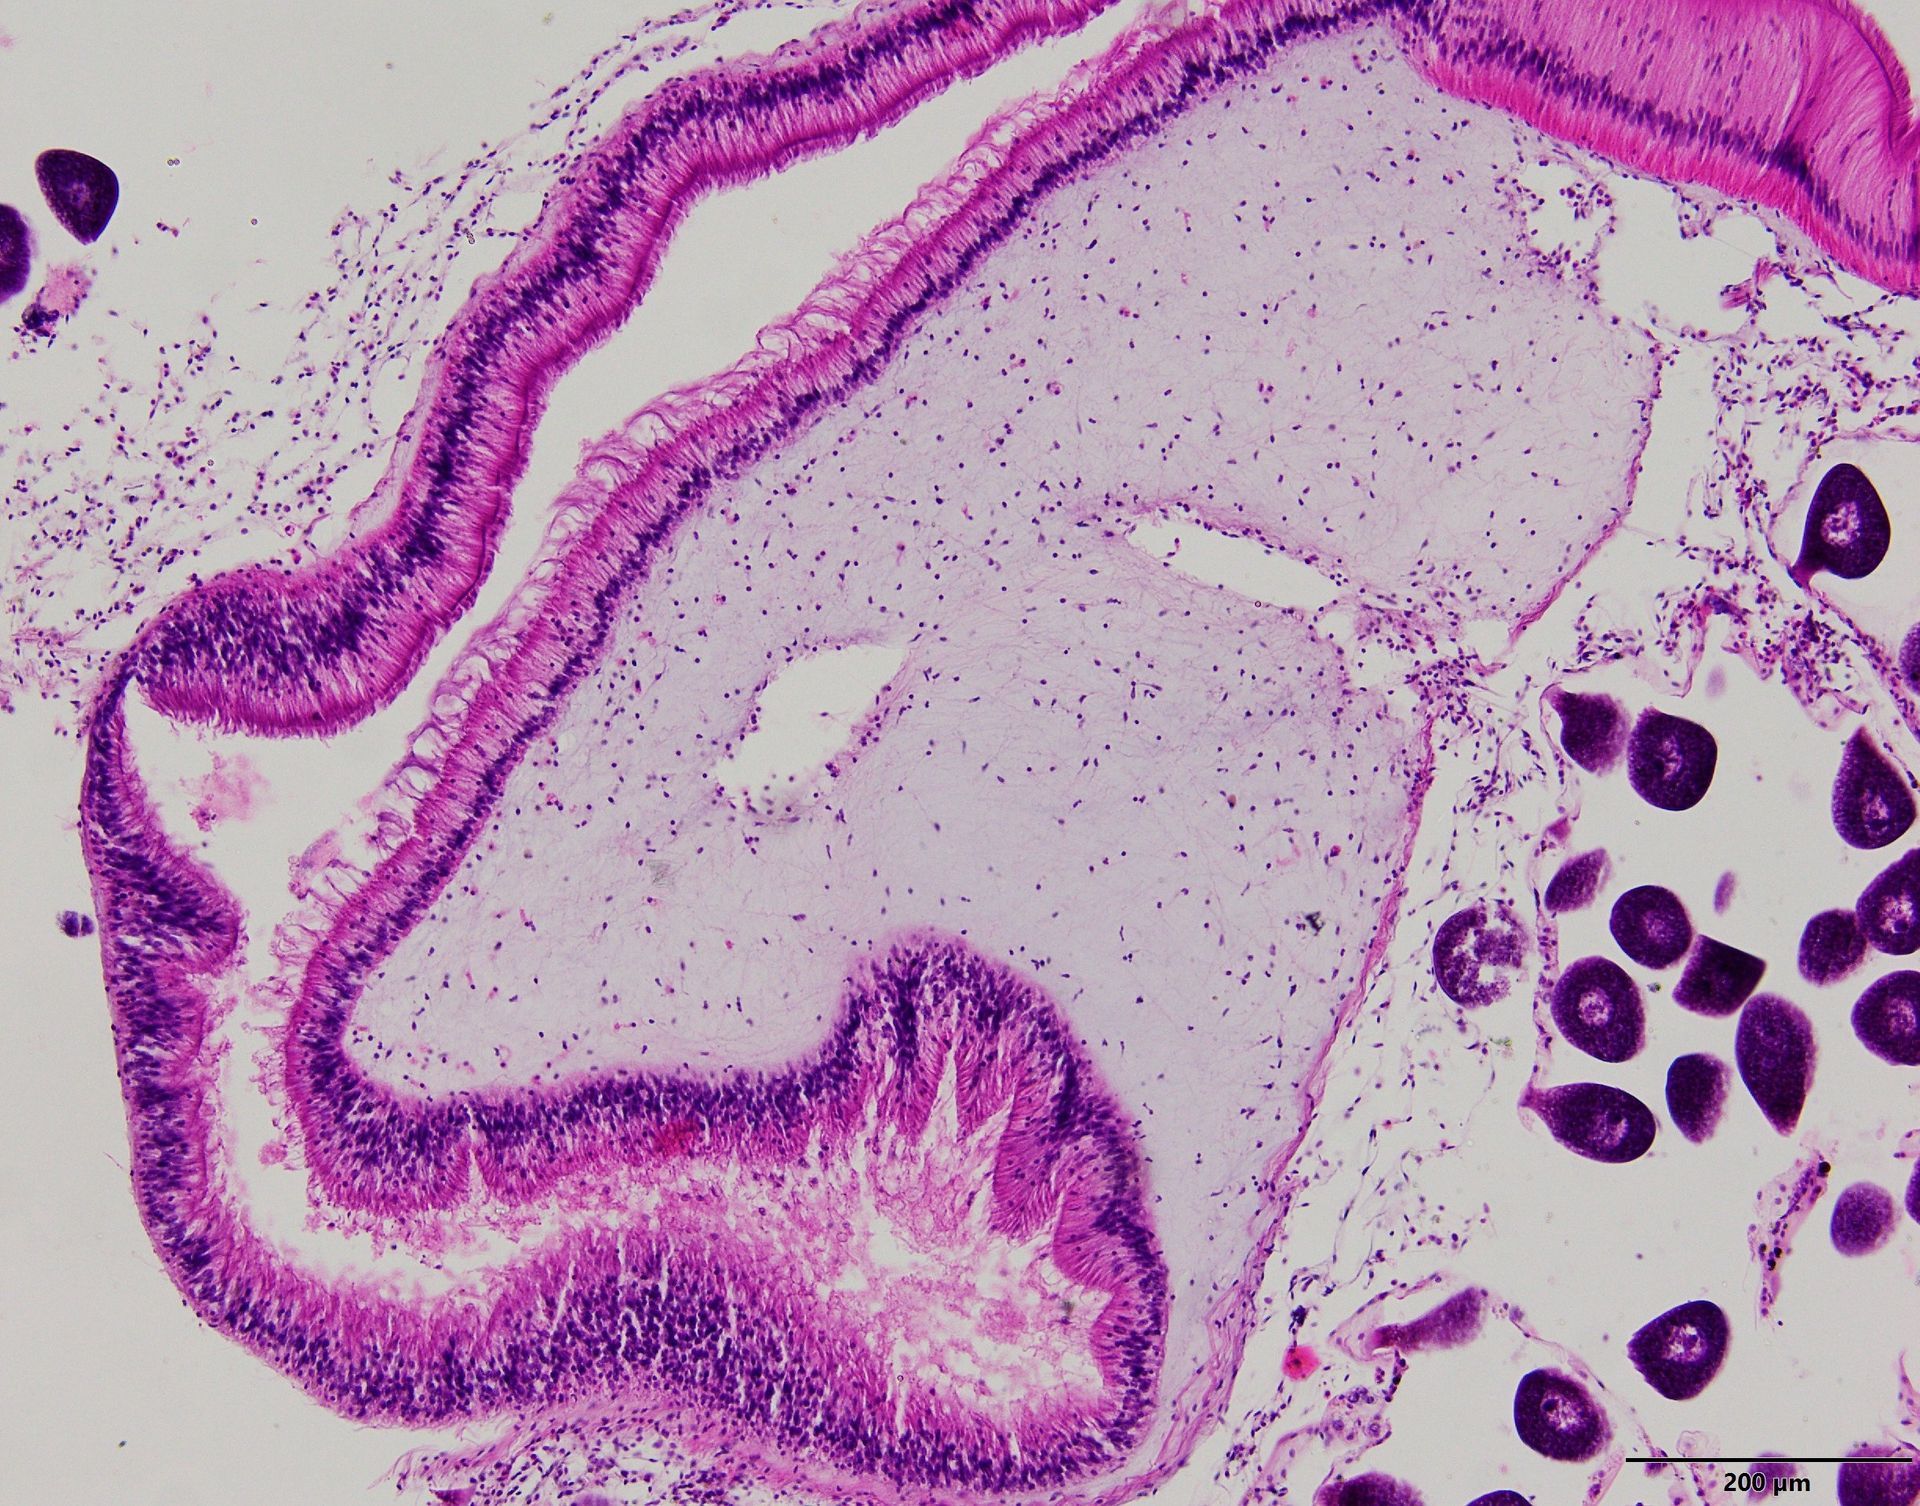

En Centro de Diagnóstico Bichat realizamos estudios histopatológicos y citológicos que permiten identificar con precisión enfermedades en tejidos y órganos de pequeños y grandes animales. Nuestros servicios incluyen:

Biopsias: análisis detallado de tejidos para confirmar, orientar o descartar diagnósticos.

Citologías: estudios rápidos y menos invasivos para orientar el tratamiento.